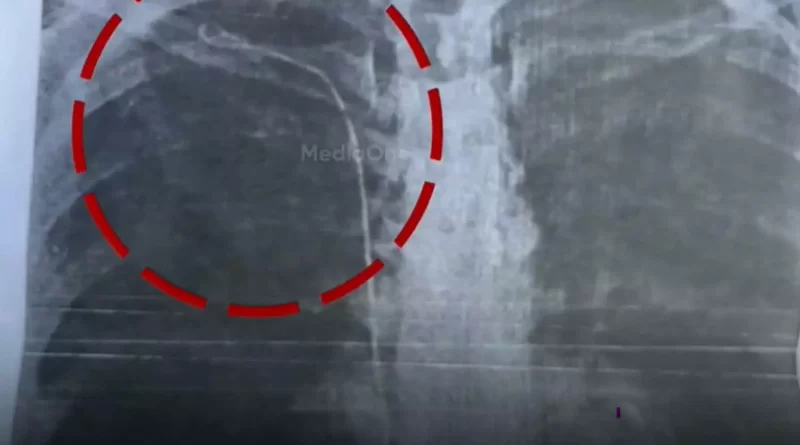

തിരുവനന്തപുരം: ജനറൽ ആശുപത്രിയിൽ ശസ്ത്രക്രിയയിൽ വീഴ്ച ഉണ്ടായെന്ന് സമ്മതിച്ച് ഡോക്ടർ.നെഞ്ചിൽ സർജിക്കൽ ട്യൂബ് കുടുങ്ങിയെന്ന മലയിൻകീഴ് സ്വദേശിനി സുമയ്യയുടെ പരാതിയിലാണ് ഡോക്ടർ വീഴ്ച സമതിച്ചത്.

ഡോ. രാജീവ് കുമാർ രോഗിയുടെ ബന്ധുവുമായി സംസാരിക്കുന്ന ശബ്ദ രേഖ പുറത്ത് വന്നു. പറ്റിയത് തെറ്റു തന്നെയാണെന്നും എന്നാല് താനല്ല അത് ചെയ്തതെന്നും അതിനെ കുറിച്ച് അറിയില്ലെന്നും ശ്രീചിത്രയിൽ കാണിക്കാനും ഡോക്ടര് പറയുന്നുണ്ട്. ആശുപത്രി ഉത്തരവാദിത്തം ഏറ്റെടുക്കേണ്ടി വരുമെന്നും ഡോക്ടർ ശബ്ദരേഖയിൽ പറയുന്നു.ശസ്ത്രക്രിയ നടത്തിയത് തിരുവനന്തപുരം ജനറല് ആശുപത്രിയിലെ ഡോക്ടര് രാജീവ് കുമാറാണെന്നാണ് സുമയ്യയുടെ ബന്ധുക്കള് പറയുന്നത്. പിഴവിൽ പൊലീസിൽ പരാതി നൽകാനൊരുങ്ങുകയാണ് കുടുംബം .